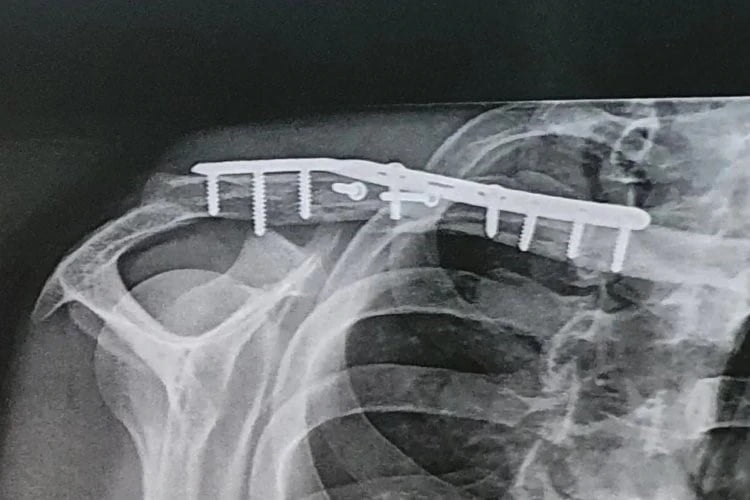

Et celle dont souffre le pilote Yamaha est du genre qu’il vaut mieux éviter. On le voit sur les clichés de son épaule, l’intérieur de Christophe Ponsson était littéralement en miette après son accident à Misano. La chirurgie qui a suivi a donc été complexe et la reconstruction prendra du temps. On rappellera que le prochain rendez-vous de la catégorie réservée aux machines issues de la série aura lieu à Donnington, les 15, 16 et 17 juillet.

« Ce n’était pas une simple clavicule cassée », a déclaré Ponsson. « Avant que la reconstruction avec une plaque et dix vis ne soit possible, il fallait couper les muscles et les nerfs pour remettre les morceaux d’os au bon endroit. Je travaille tous les jours avec mon kiné pour être aussi en forme que possible pour la prochaine course en Angleterre dans un peu plus de deux semaines » termine le troisième tricolore du plateau avec Loris Baz et Lucas Mahias, par ailleurs lui-même convalescent d’une autre blessure subie en course.